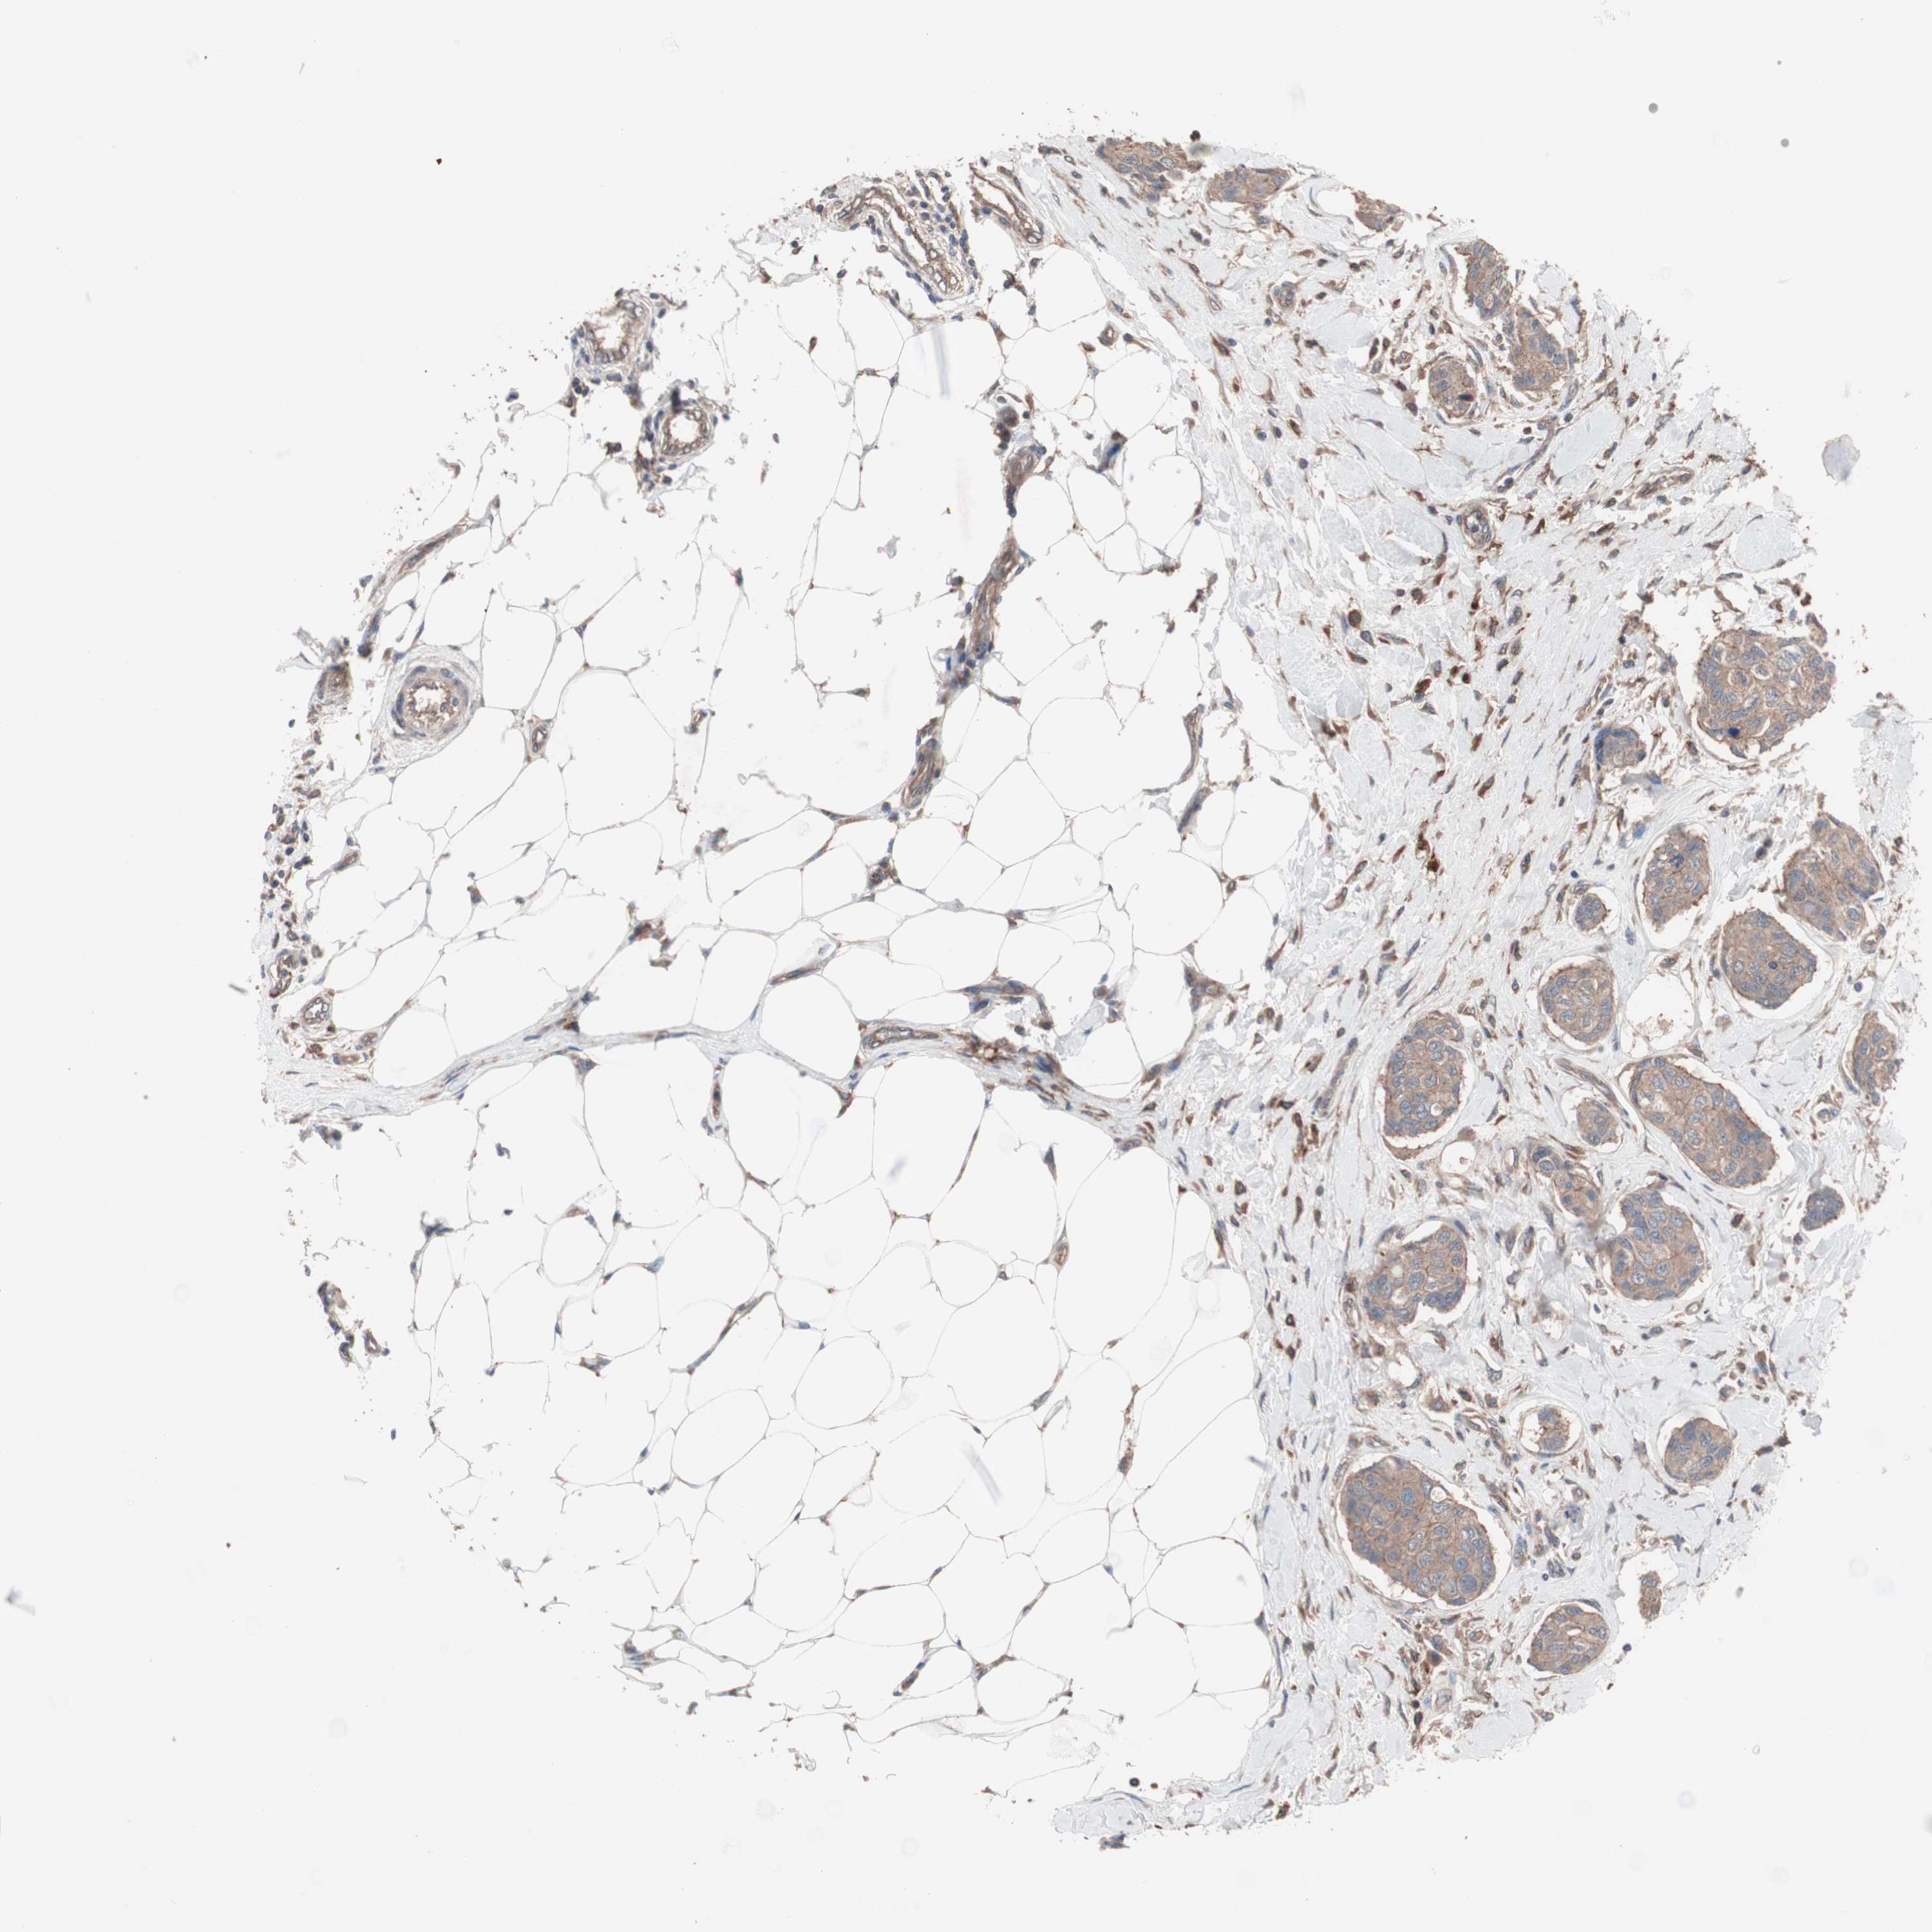

CANCER BREAST CANCER Show tissue menu

BRCA TCGA BRCA VALIDATION PROTEIN EXPRESSION

ANTIBODIES

AND

VALIDATION